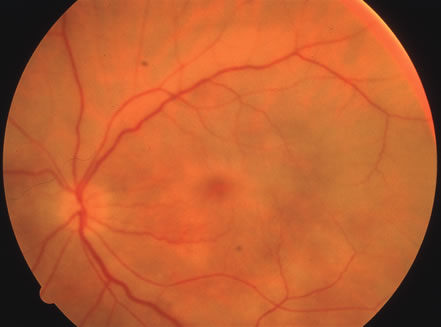

The acute retinal necrosis (ARN) syndrome is most often caused by the herpes zoster virus, although occasionally it may be a result of herpes simplex infection.12 It is typically described in healthy patients although association with immunosuppressed patients has also been described. Granular, nonhemorrhagic areas of retinal necrosis may be observed in the fundus, often rapidly coalescing with resulting blindness often caused by retinal detachment. There is often an associated vasculitis and vitritis. In immunocompromised patients VZV or HSV retinitis may also take the pattern of progressive outer retinal necrosis (PORN) (Fig. 6). PORN differs from ARN in that the former is multifocal, localized to the outer retina, and is less often associated with vasculitis and vitritis.